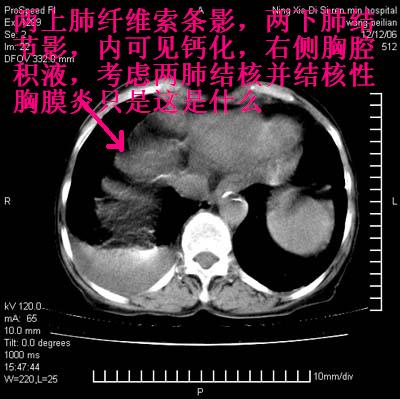

两肺尖纤维索状影,两下肺结节块状影,且有钙化灶,右胸腔积液。考虑肺结核并胸膜炎。

两肺尖纤维索状影,两下肺结节块状影,且有钙化灶,右胸腔积液。考虑肺结核并胸膜炎肺间质纤维化

以下是引用lizhenhua_00在2006-12-13 20:12:00的发言:[br]两肺尖纤维索状影,两下肺结节块状影,且有钙化灶,右胸腔积液。考虑肺结核并胸膜炎。

双肺见多个结节状及条索状影,双侧胸腔积液,右侧叶间积液,考虑结核性胸膜炎

肺结核并右侧结核性胸膜炎

双侧肺结核伴右侧胸腔积液.